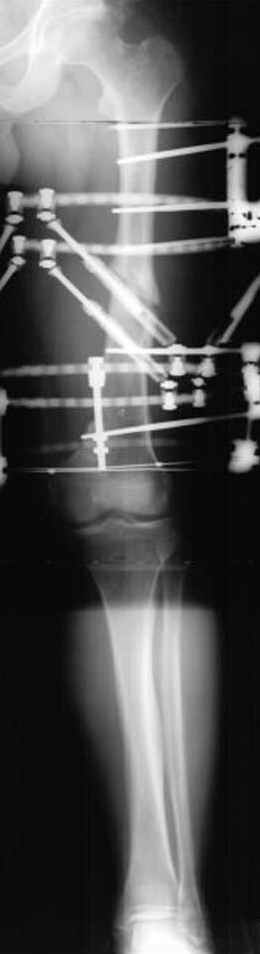

Отправитель: Djoldas Kuldjanov 23 Ноябрь 2004, 18:21

пластическая модель; и коррекция бедра аппаратом Илизарова.

Имею другие снимки тоже, получится как отчет о моей работе.

Почему не замена гвоздя с рассверливанием, а аппарат?

Отправитель: Alexander Chelnokov 23 Ноябрь 2004, 21:29

хотя даже если бы и инфекция , то nail exchange с рассверливанием канала - вариант дебрайдмента) Я думаю, что последовательность развития событий:

Узкий к-м канал - тонкий гвоздь- усталостный перелом дистальных винтов - развитие нестабильности и как ее результат остеолиз вокруг гвоздя - деформация анатомической оси бедра. Похоже, что я понял почему аппарат, а не новый гвоздь:-)